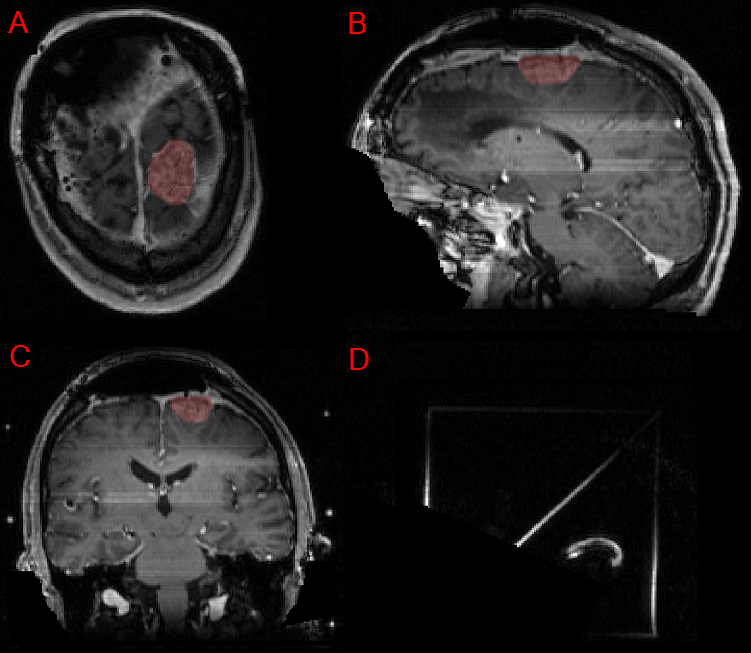

Figure 3: Panels A, B, and C showing a postoperative left parietal meningioma target volume (red) in the axial, sagittal, and coronal planes, respectively, as delineated by the treating institution.

Refer to caption